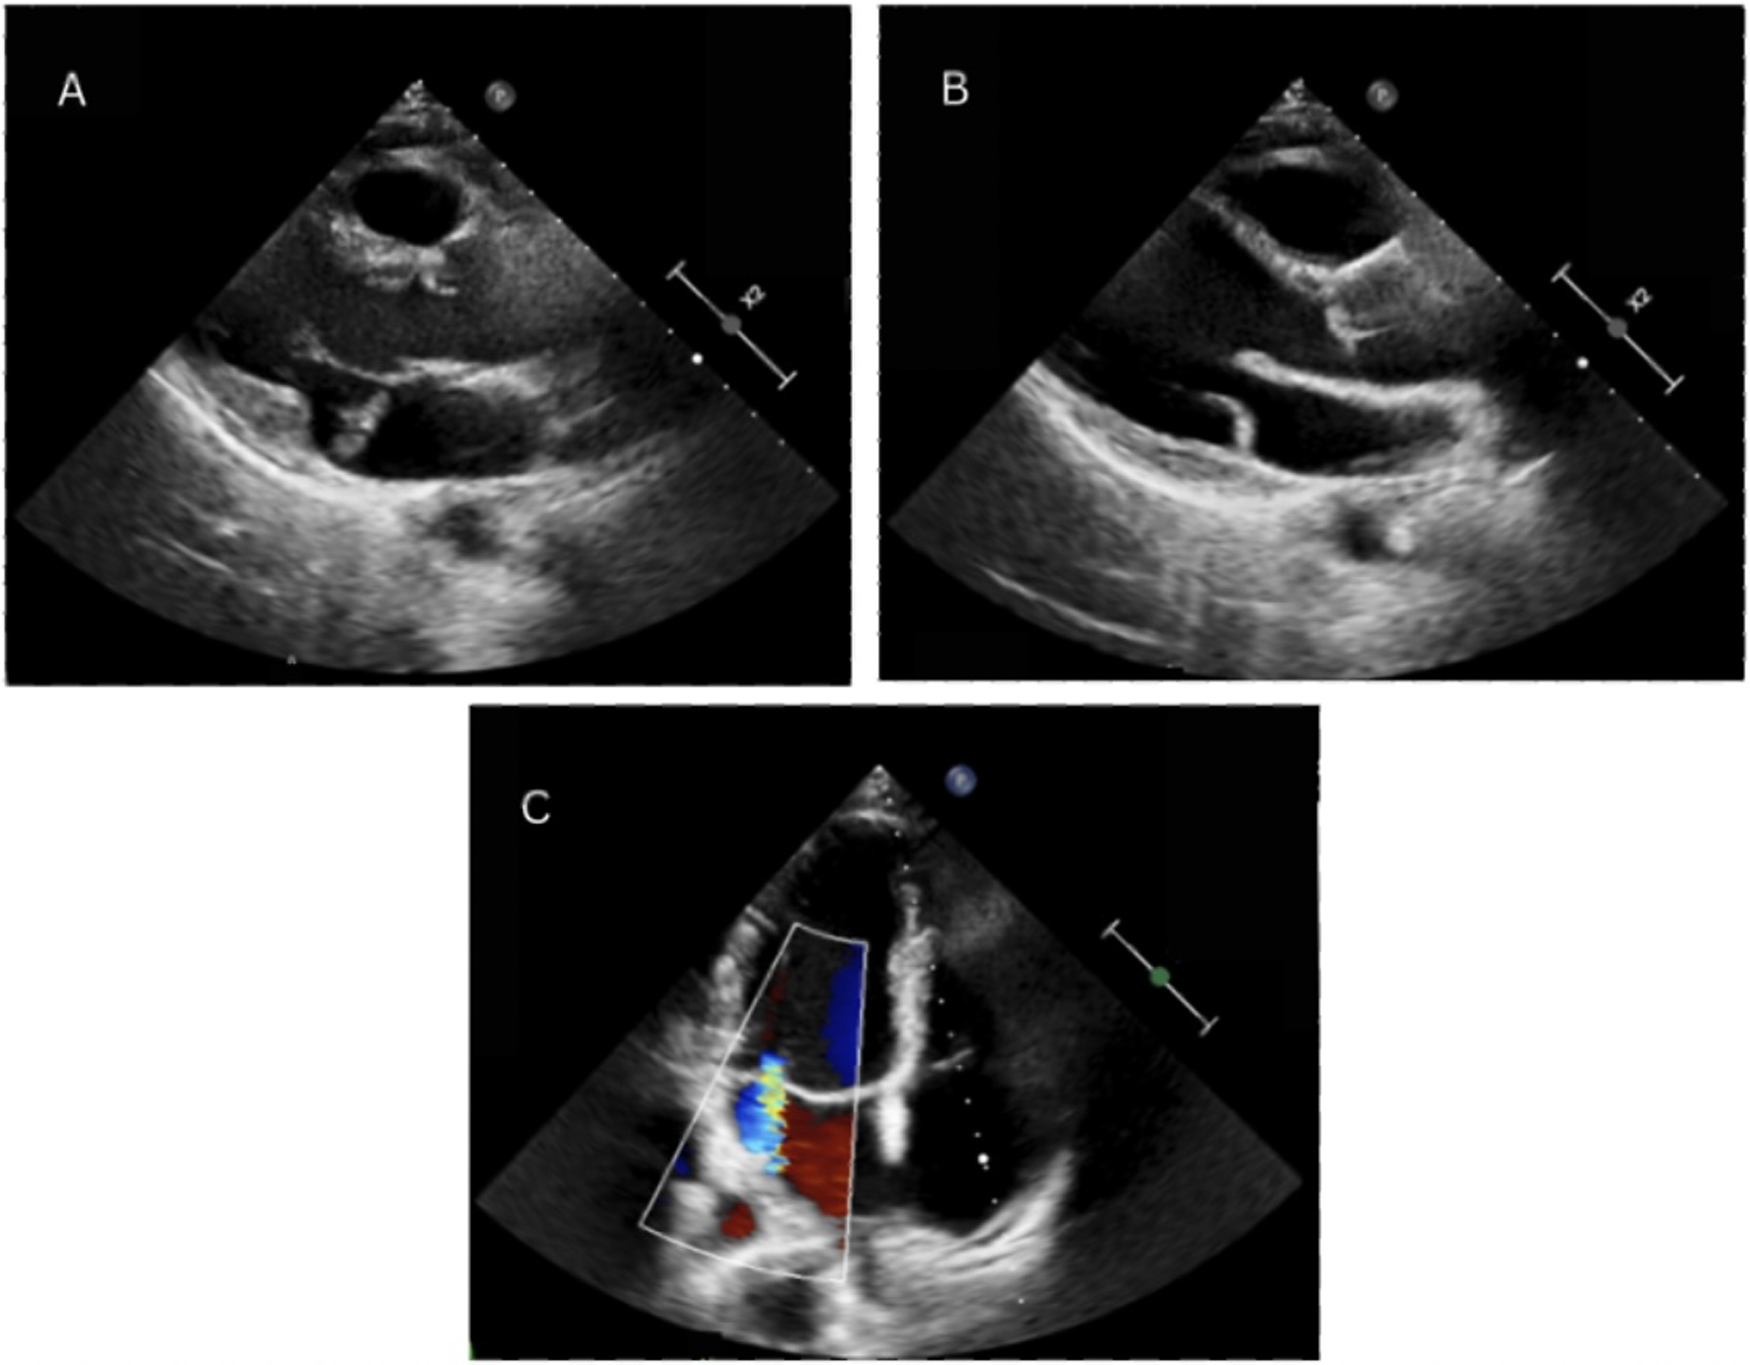

TTE was also performed to reveal normal diameters and functions of all heart chambers, bileaflet MVP and moderate MVR, which can be seen in Figure 1. To rule out underlying structural heart disease, CMR was performed, which confirmed MVP with moderate MVR, also revealing the presence of MAD. No LGE was detected, indicating the absence of myocardial fibrosis. Subsequently, the patient was hospitalized for three days for a 72 h HM and treatment planning. During the hospitalization no episodes of ventricular tachycardia (VT) were recorded, and the daily burden of PVCs ranged between 600 and 800. The patient's medical data were reevaluated by a team of electrophysiologists who concluded that, despite the absence of myocardial fibrosis and no currently documented episodes of VT, long-term rhythm monitoring was necessary. This decision was based on the 2022 ESC guidelines, which support ILR implantation (Class IIa) in patients with a history of unexplained syncope or prior VAs, even in the absence of conventional high-risk markers (6). In this case, ILR implantation was justified by the patient's history of previously recorded VT episodes and syncope, her engagement in regular intense physical activity, and the presence of arrhythmogenic mitral valve features (including MAD and PVC morphology suggestive of papillary muscle origin).

Figure 1

Echocardiography demonstrating mitral annular disjunction. Parasternal long-axis view obtained at end-systole and diastole, showing the separation between the posterior mitral valve leaflet insertion point and the left ventricular myocardium (A,B). Color Doppler imaging visualizing mitral regurgitation, evidenced by a central regurgitant jet (C).